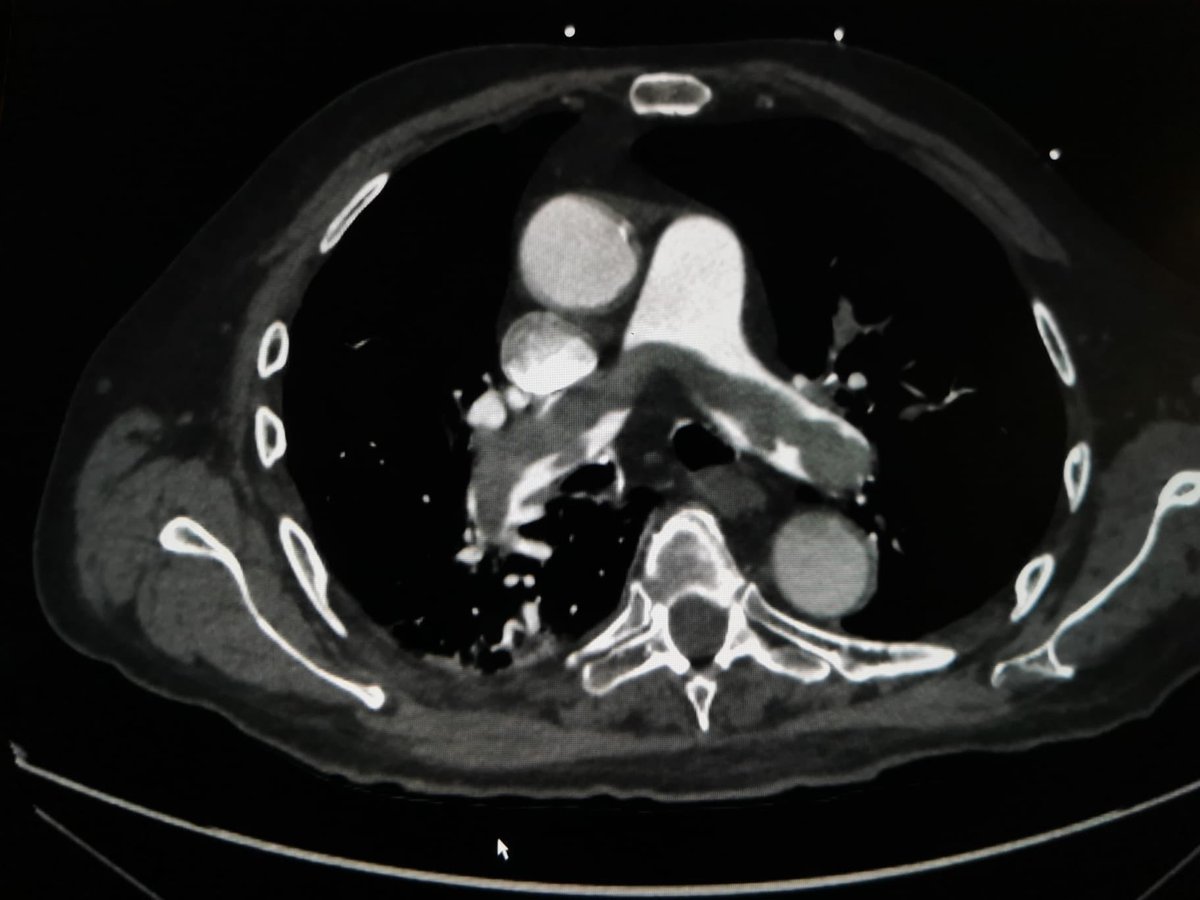

65 yo man with lung cancer and a craneal metastases removed 10 days ago. Sat O2 92% HR 110 bpm, SBP 90 mmHg. What would you do? ⁦

8

37

129